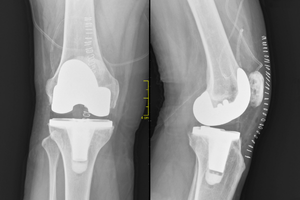

How this tech could transform joint replacements forever

A pioneering material developed at Flinders University is set to transform orthopaedic surgery by tackling two major challenges: infection and implant longevity.